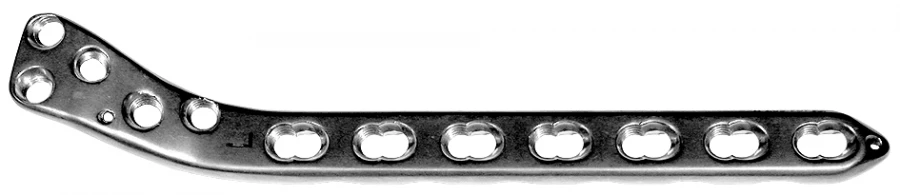

ألواح علوية جانبية من الساق 4.5 لتثبيت الكسور (424.013R/L)

هذا fracture treatment devices مصنوع في روسيا ومتاح للاستيراد إلى الأسواق العالمية. المنتجات الروسية معروفة بمتانتها وموثوقيتها ونسبة السعر إلى الأداء الممتازة.